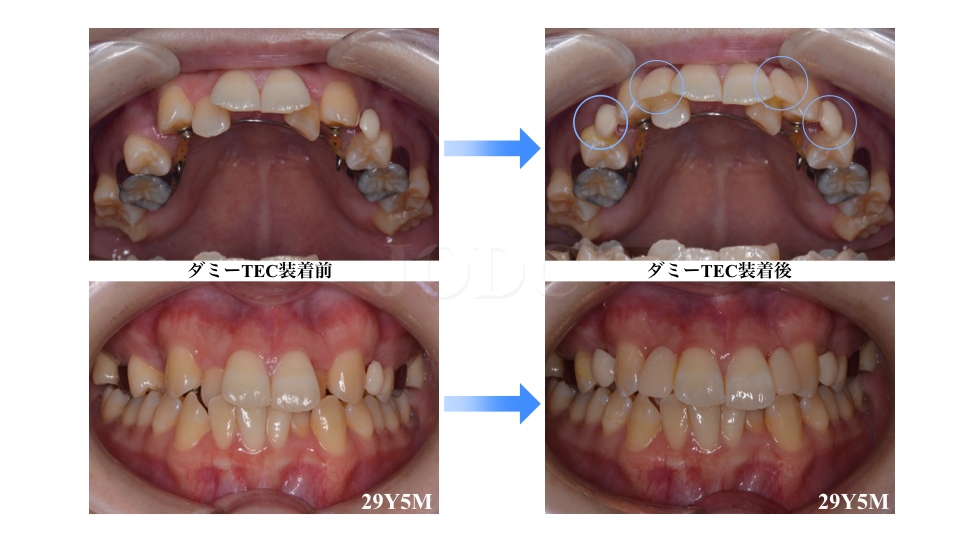

矯正動的治療途中に結婚式を迎えることとなりましたので、結婚式直前に上の前歯と小臼歯に一時的にダミーTEC計4本分の装着を行いました。

結婚式終了後ダミーTECの除去を行い、下顎MBS装置完了時口腔内写真です。